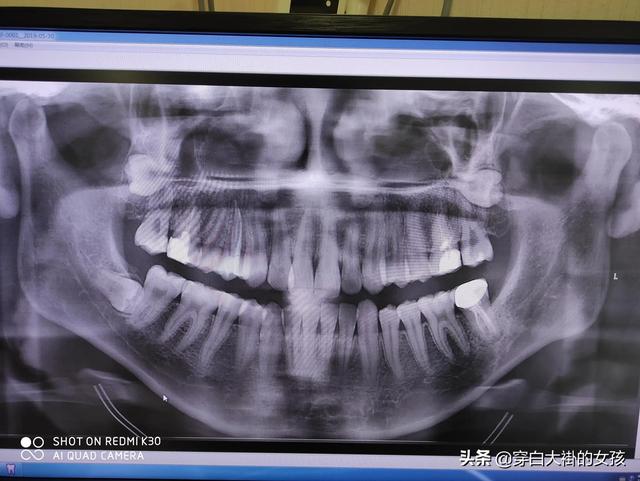

치아는 인체의 중요한 기관으로, 음식을 씹는 것 외에도 치아의 주요 기능은 얼굴의 미를 유지하고 조정을 하며 발음을 돕는 것입니다.

치아의 기능 - 씹기

- 음식을 삼키기 쉽도록 잘게 찢어주세요;

- 씹는 과정은 치아 뿌리 주변의 신경을 자극하여 뇌가 연동 운동을 반사적으로 조절하도록 자극합니다. 동시에 담낭과 췌장에서 소화액 분비를 촉진하여 소화를 더욱 촉진합니다.

치아의 기능-조절에 도움을 줍니다.

- 소리는 성대에서 생성되고 입과 비강을 비롯한 여러 기관의 조정을 거쳐 우리가 이해할 수 있는 언어로 만들어집니다.

- 치아가 없으면 말이 어눌해집니다. 치아가 없으면 말이 새어 나옵니다.

치아의 기능-얼굴 미학과 조화 유지

사람 얼굴의 시각적 인식의 60-70 %는 얼굴의 아래쪽 1/3에서 비롯되며, 치아가 가지런하지 않거나 입이 튀어 나오거나 바오 티안 등이 있으면 얼굴의 아래쪽 1/3이 좋지 않습니다. "얼굴의 상반부는 아름다움을 결정하고 얼굴의 하반부는 추함을 결정한다"는 말이 있는데, 다섯 가지 특징의 윤곽이 아무리 좋더라도 심각한 입 돌출 문제가있는 한 기질을 강조하기가 매우 어려울 것입니다. 외모가 좋지 않다고 생각하고 치아가 없거나 고르지 않은 치아도 있다면 얼굴 가치가 더욱 떨어질 것입니다.